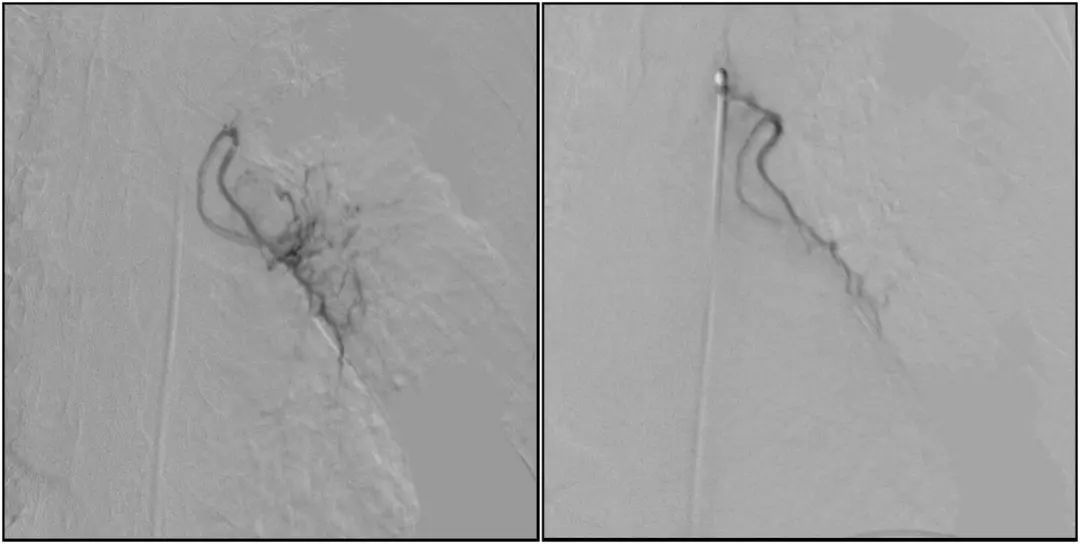

支气管动脉栓塞+化疗灌注术

在普爱医疗移动式平板介入中C影像的引导下,医生为患者实施双侧支气管动脉栓塞+化疗灌注术。

在微导丝的配合下,先后分别超选择①至3支左侧支气管动脉肿瘤供血动脉,经微导管推注栓塞微粒球栓塞肿瘤动脉。栓塞结束后,再次用移动式平板介入中C做造影检查,见肿瘤染色消失。

术前术后对比影像